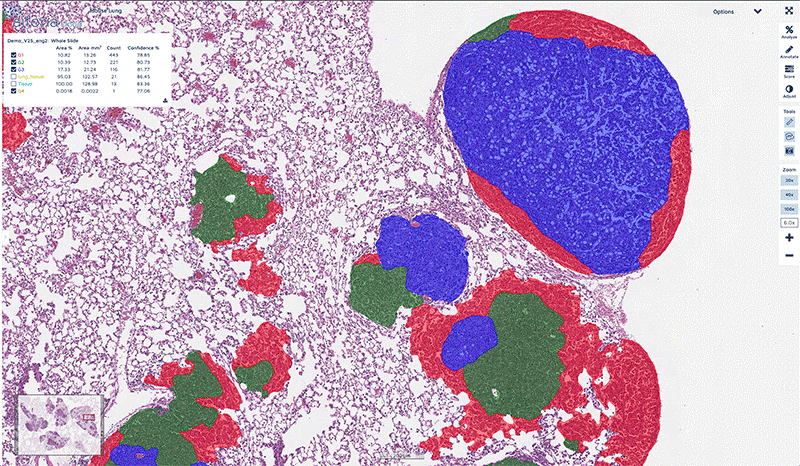

Aiforia segmentation

The Aiforia platform enables you to see more — outperforming and even surpassing human capacity in image analysis. Aiforia’s AI models can successfully complete a wide range of image analysis tasks with higher accuracy, sensitivity and speed.